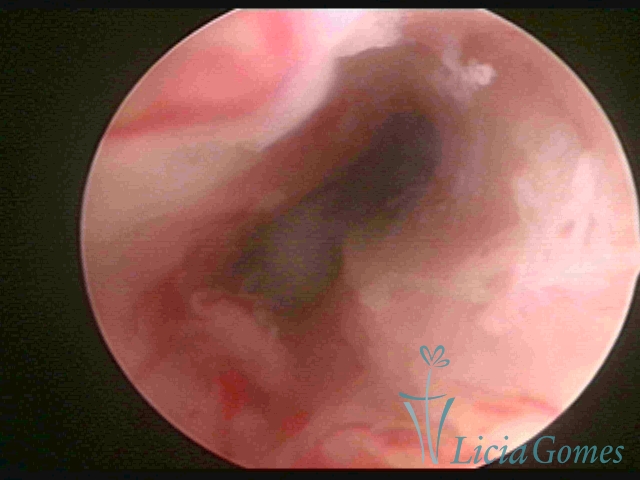

Segunda porção ou setor médio

No terço ou setor médio do canal cervical perdemos o detalhe das papilas, sendo possível a visualização de pregas e criptas. Normalmente observamos os sulcos longitudinais, que são os tecidos mais compactos, com a superfície mais vascularizada, cujos vasos seguem o seu trajeto.